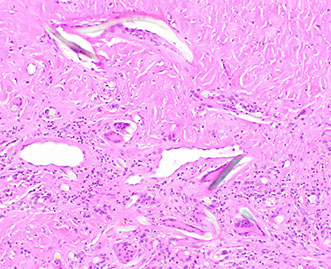

Elastosis / Elastofibromatous change

Inc focal or diffuse elastic fibers in submucosa or muscularis mucosa, which manifests as a polyp

- B9, no clinical action needed

Micro: looks like finely granular c fibrillary amphophilic material, sometimes elastofibromatous change (fibrous component), usually around BVs and sometimes mistaken as amyloid (elastin pos, Congo red neg)